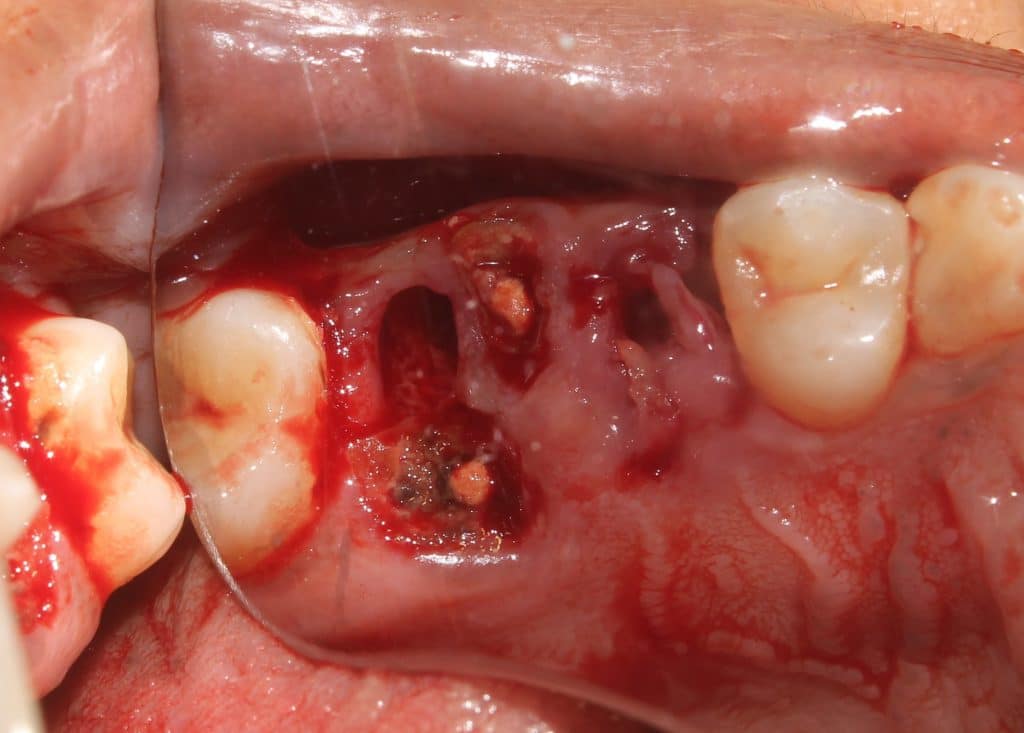

same is followed for mesial root..

followed by palatal root..

final photograph shows good preservation of furcal bone and buccal plate..